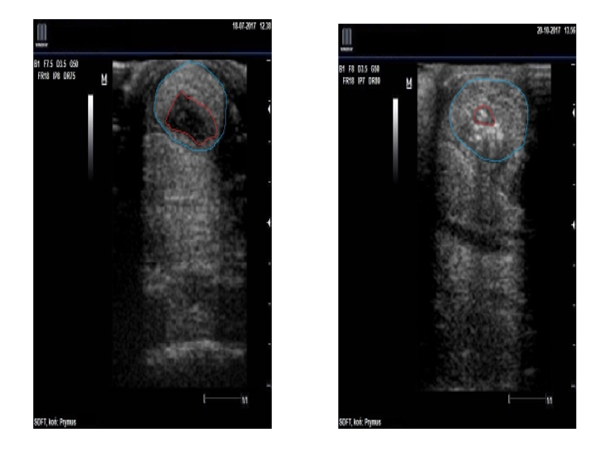

W pierwszych dniach często obserwujemy zmniejszenie tkliwości palpacyjnej i obwodu obrzęku. W USG, po kilku tygodniach, celem jest poprawa echogeniczności i redukcja hipoechogenicznych „kieszeni”, z równoległą poprawą wzorca włókien. Decyzja o powrocie do treningu opiera się na kryteriach obiektywnych: brak kulawizny, testy funkcjonalne, akceptowalna odpowiedź ścięgna na obciążenia następnego dnia (brak reaktywnego obrzęku).